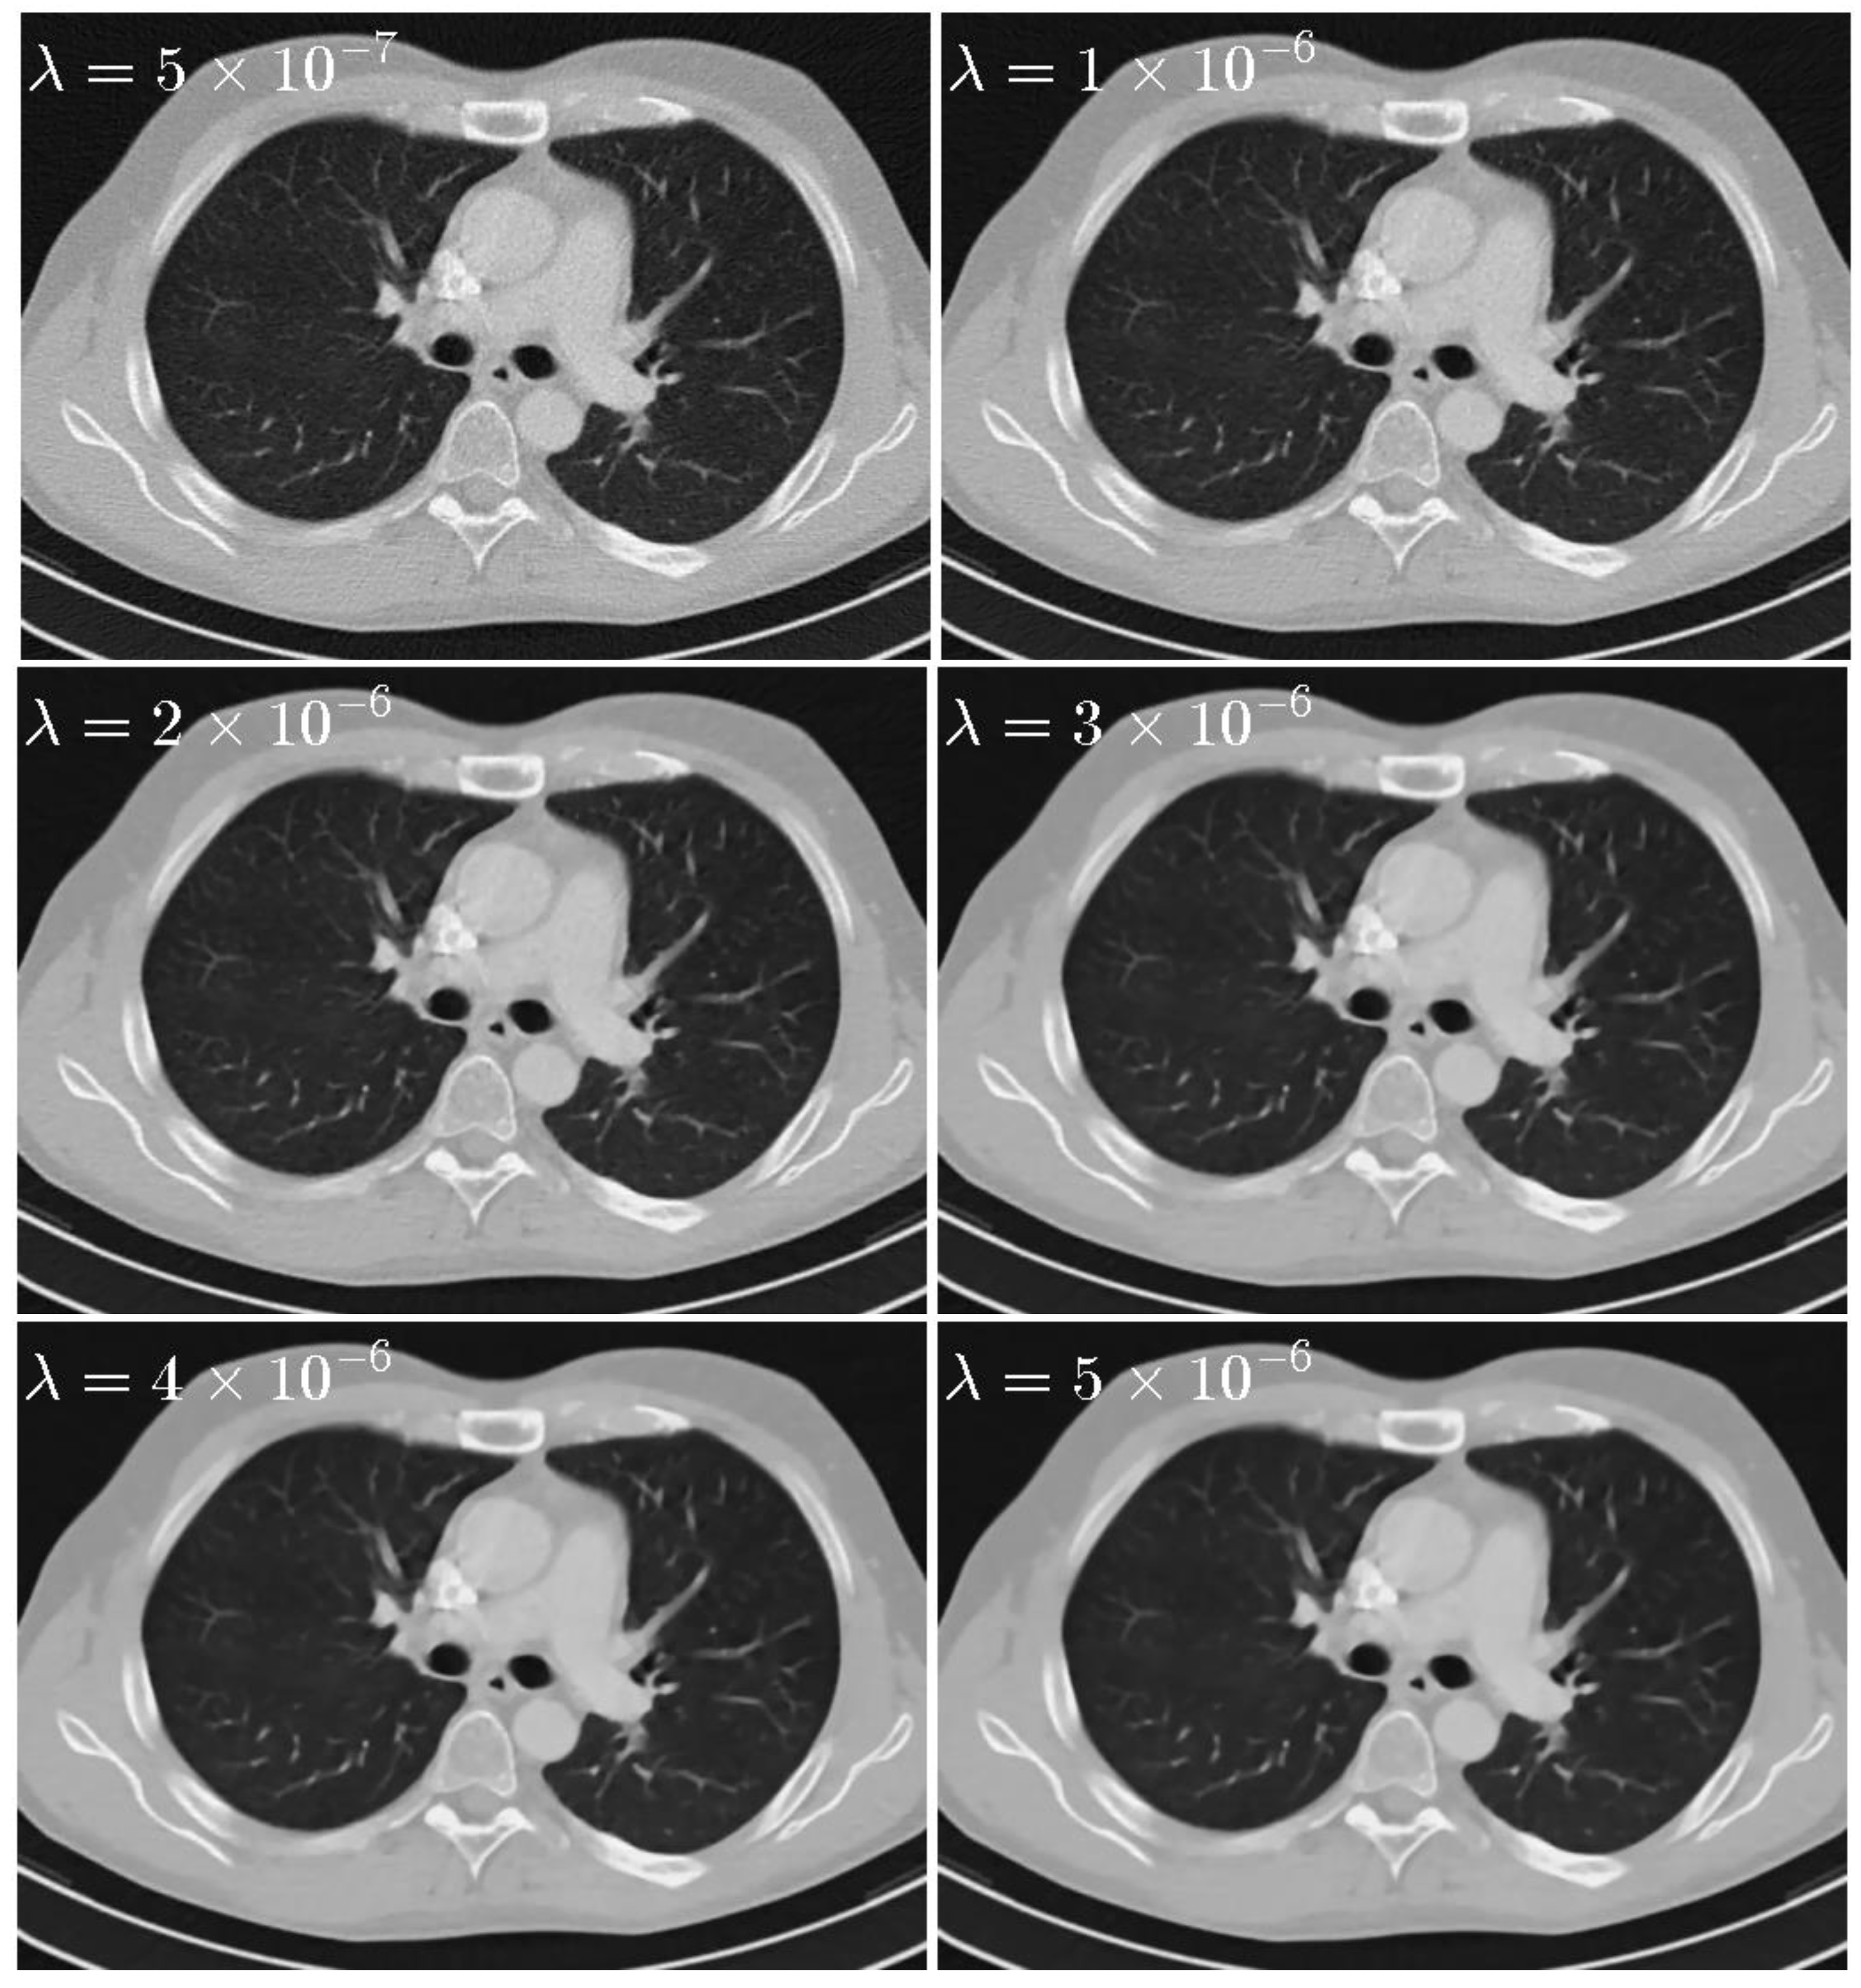

(1) Regularization parameter λ : To sense the sensitivity of λ , experiments are performed with various λ = 5 × 10 7 , 1 × 10 6 , 2 × 10 6 , 3 × 10 6 , 4 × 10 6 , and 5 × 10 6 with σ = 0.5 , L K = 3 . The reconstruction images are shown in Figure 6. The PSNR, RRE, and SSIM curves corresponding to different λ are plotted in Figure 7. It is clear that the value of PSNR and SSIM are highest and the value of RRE is lowest when λ = 2 × 10 6 .

Figure 6. Thorax images reconstructed by the SIR-STV1 method with respect to different λ . The display window is [−1000, 667] HU.

Sensors 20 01647 g006